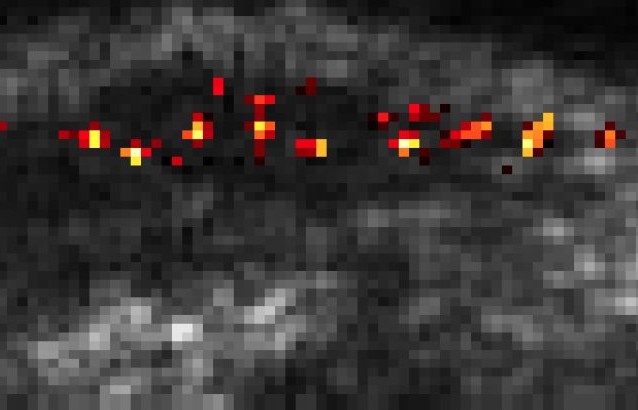

Single cells traveling through the liver of a mouse. Caltech/Daniel Sawyer, Shapiro Lab